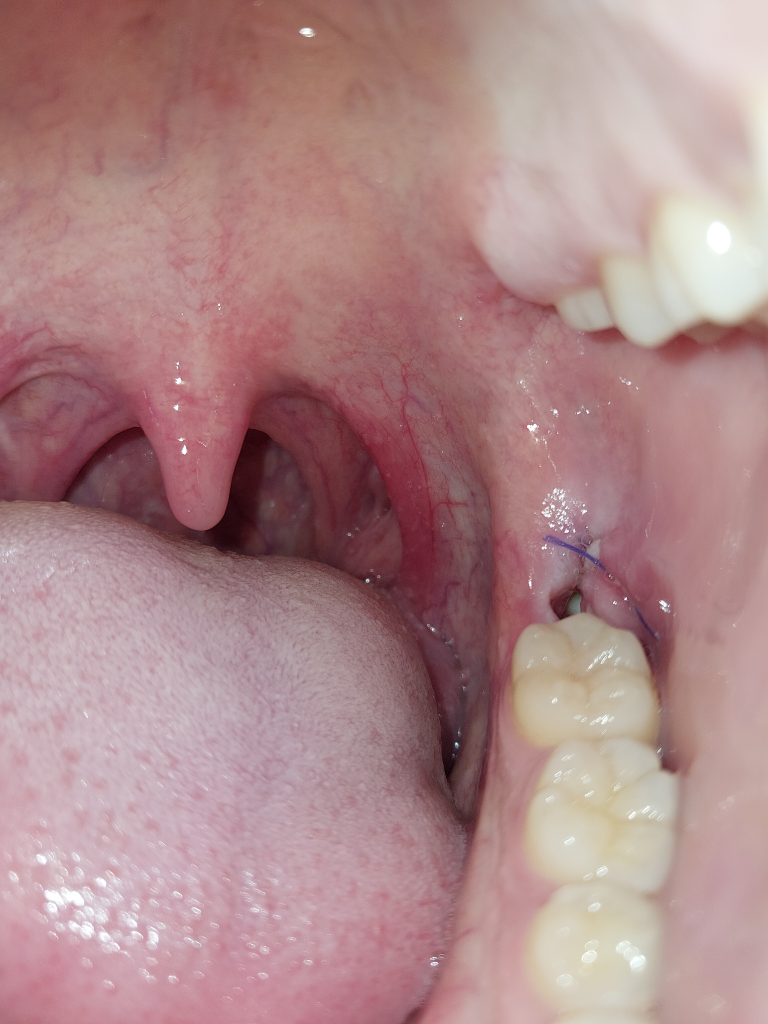

사랑니 발치 자리에 혈병은 기간이 얼마나 지나야만 떨어지나요?

발치한지 5일됬습니다 아침에 일어나서 보니까 조금 남아있던 혈병이 사라졌고 구멍만 보이는데 지금 떨어져도 상관없나요? 그리고 구멍안에 하얀게 보이는데 저건 뭔가요?

• 1번 째 사진

네 혈병이 떨어지는 것은 자연스러운 현상입니다. 그안에 하얀것은 잇몸이 아물고 있는 과정으로 보이며, 잇몸이 차오르는데까지는 3-6개월 이상 시간이 소요될수 있습니다.

발치 직후 2시간정도부터 출혈이 멈추면 혈병(흔히 말하는 피떡)이 생깁니다. 이제 그러면 출혈은 멈추고 혈액이 응고되고 혈액에 있는 다양한 세포가 조직을 재생하게 됩니다. 발치후 4일부터는 혈병은 아래 조금 깔려있고 육아조직이 생기고 상피세포(표면 잇몸)가 자라기 시작합니다. 그러면서 일주일 정도되면 발치 공간이 닫힙니다. 이때 봉합을 풀어주고요. 현재 별다른 통증이 없다면 정상적인 치유과정중입니다. 하얀 건 육아조직과 골양조직(초기 골조직)으로 보여지므로 정상입니다. 아직까지 치유과정이 완료되려면 먼 길이 남았습니다. 앞으로 유골(골양조직)이 단단해지면서 진짜 뼈로 되고 결합조직도 재생이 되어야 하는데 이 과정이 2~3개월 정도 걸립니다.

걱정하시는 드라이소켓 등은 극심한 통증이 동반됩니다. 만약 통증이나 악취가 동반된다면 치과에 내원하시기 바랍니다.